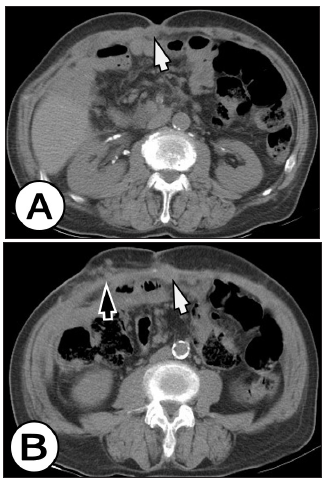

Figure 1: Axial MDCT without the intravenous contrast. (A) CT scan showed a mass at the umbilicus, (white arrow). (B) CT scan showed a Mary Joseph Sister nodule (white arrow), and a distal to the umbilicus on the right side several well-circumscribed nodules were seen lying within the subcutaneous tissue of the anterior abdominal wall (black arrow).

Figure 2: Contrast-enhanced MDCT axial slices in arterial phase: CT scan showed a Mary Joseph Sister enhanced nodule (white arrow), and a distal to the umbilicus on the right side several well-circumscribed enhancing nodules were seen lying within the subcutaneous tissue of the anterior abdominal wall (black arrow). There was no evidence of recurrence of the primary tumor.